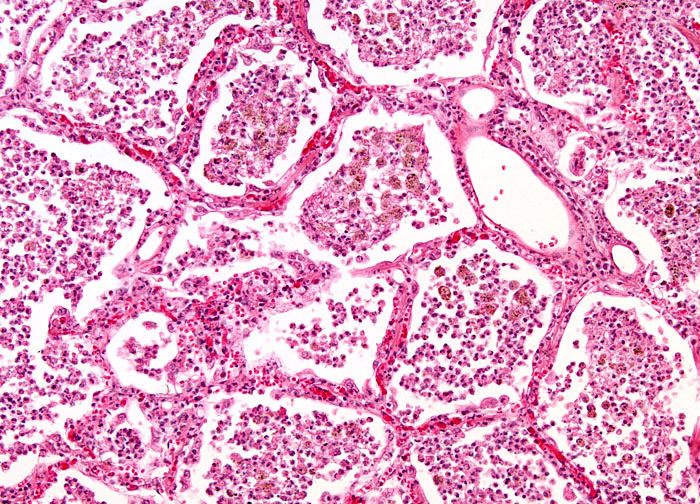

Lobar collapse demystified: the chest radiograph with CT correlation | Postgraduate Medical Journal  Lobar Pneumonia at 20x Magnification | Nikonâs MicroscopyU

Lobar Pneumonia at 20x Magnification | Nikonâs MicroscopyU  Lobar TV - Lobar Incorporated

Lobar Pneumonia, Grey Hepatic Phase Stock Photo - Image of grey, microscope: 130407010  Lobar holoprosencephaly | Radiology Case | Radiopaedia.org

lobar pneumonia - Liberal Dictionary  Lobar hemorrhage | Radiology Reference Article | Radiopaedia.org

Lobar Pneumonia vs Bronchopneumonia | eHealthStar  ENFISEMA LOBAR CONGENITO PDF

Lobar Pneumonia at 10x Magnification | MicroscopyU  Congenital Lobar Emphysema Article